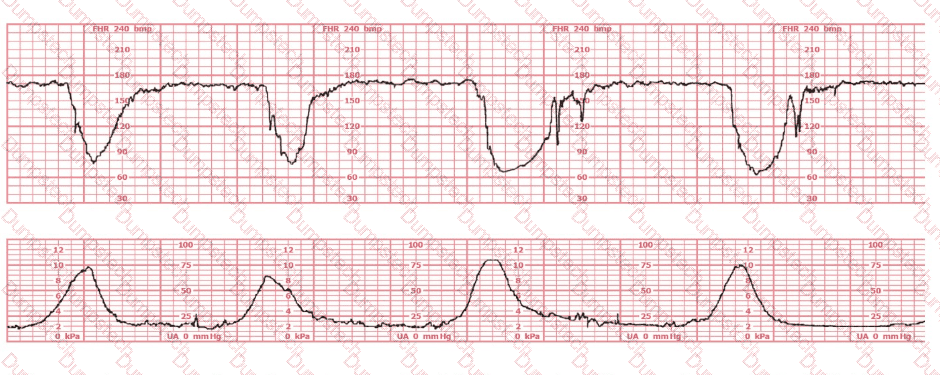

A 30-year-old woman (G2P0) is experiencing preterm labor at 26-weeks gestation. She is receiving magnesium sulfate for neuroprotection. Her external fetal monitoring tracing over the past 30 minutes is shown. The next step would be to: